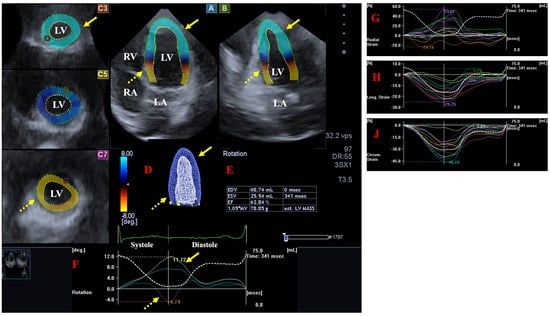

2.3. Three-Dimensional Speckle-Tracking Echocardiography

- The following LV rotational parameters were provided: apical and basal LV rotations, LV twist and time-to-peak LV twist [25].

- The following global LV strains, featuring the whole LV were measured [26]:

- LV radial strain (LV-gRS)—for characterizing thinning/thickening of the myocardial tissue.

- LV longitudinal strain (LV-gLS)—for characterizing lengthening/shortening of the myocardial tissue.

- LV circumferential strain (LV-gCS)—for characterizing widening/narrowing of the myocardial tissue.